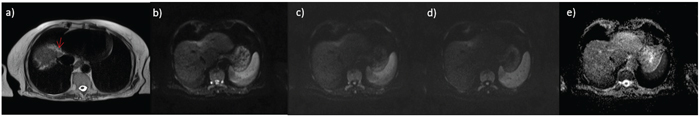

A total of 62 HCCs were evaluated (median 1.82 lesions; diameter between 12 and 20 mm). All tumors were histologically classified according to the major Edmondson-Steiner grade on final pathologic reports as follows: 14 with grade 1, 30 with grade 2, 18 with grade 3, and no one with grade 4. Figure 1, 2 and 3 report example of HCC of grade 1, 2 and 3 respectively.

Figure 1: small HCC on IV hepatic segment G1; in a. HASTE T2-wejgthed image, in b. DWI image at b value 50 s/mm2, in c. DWI image at b value 400 s/mm2, in d. DWI image at b value 800 s/mm2 and in e. ADC map.